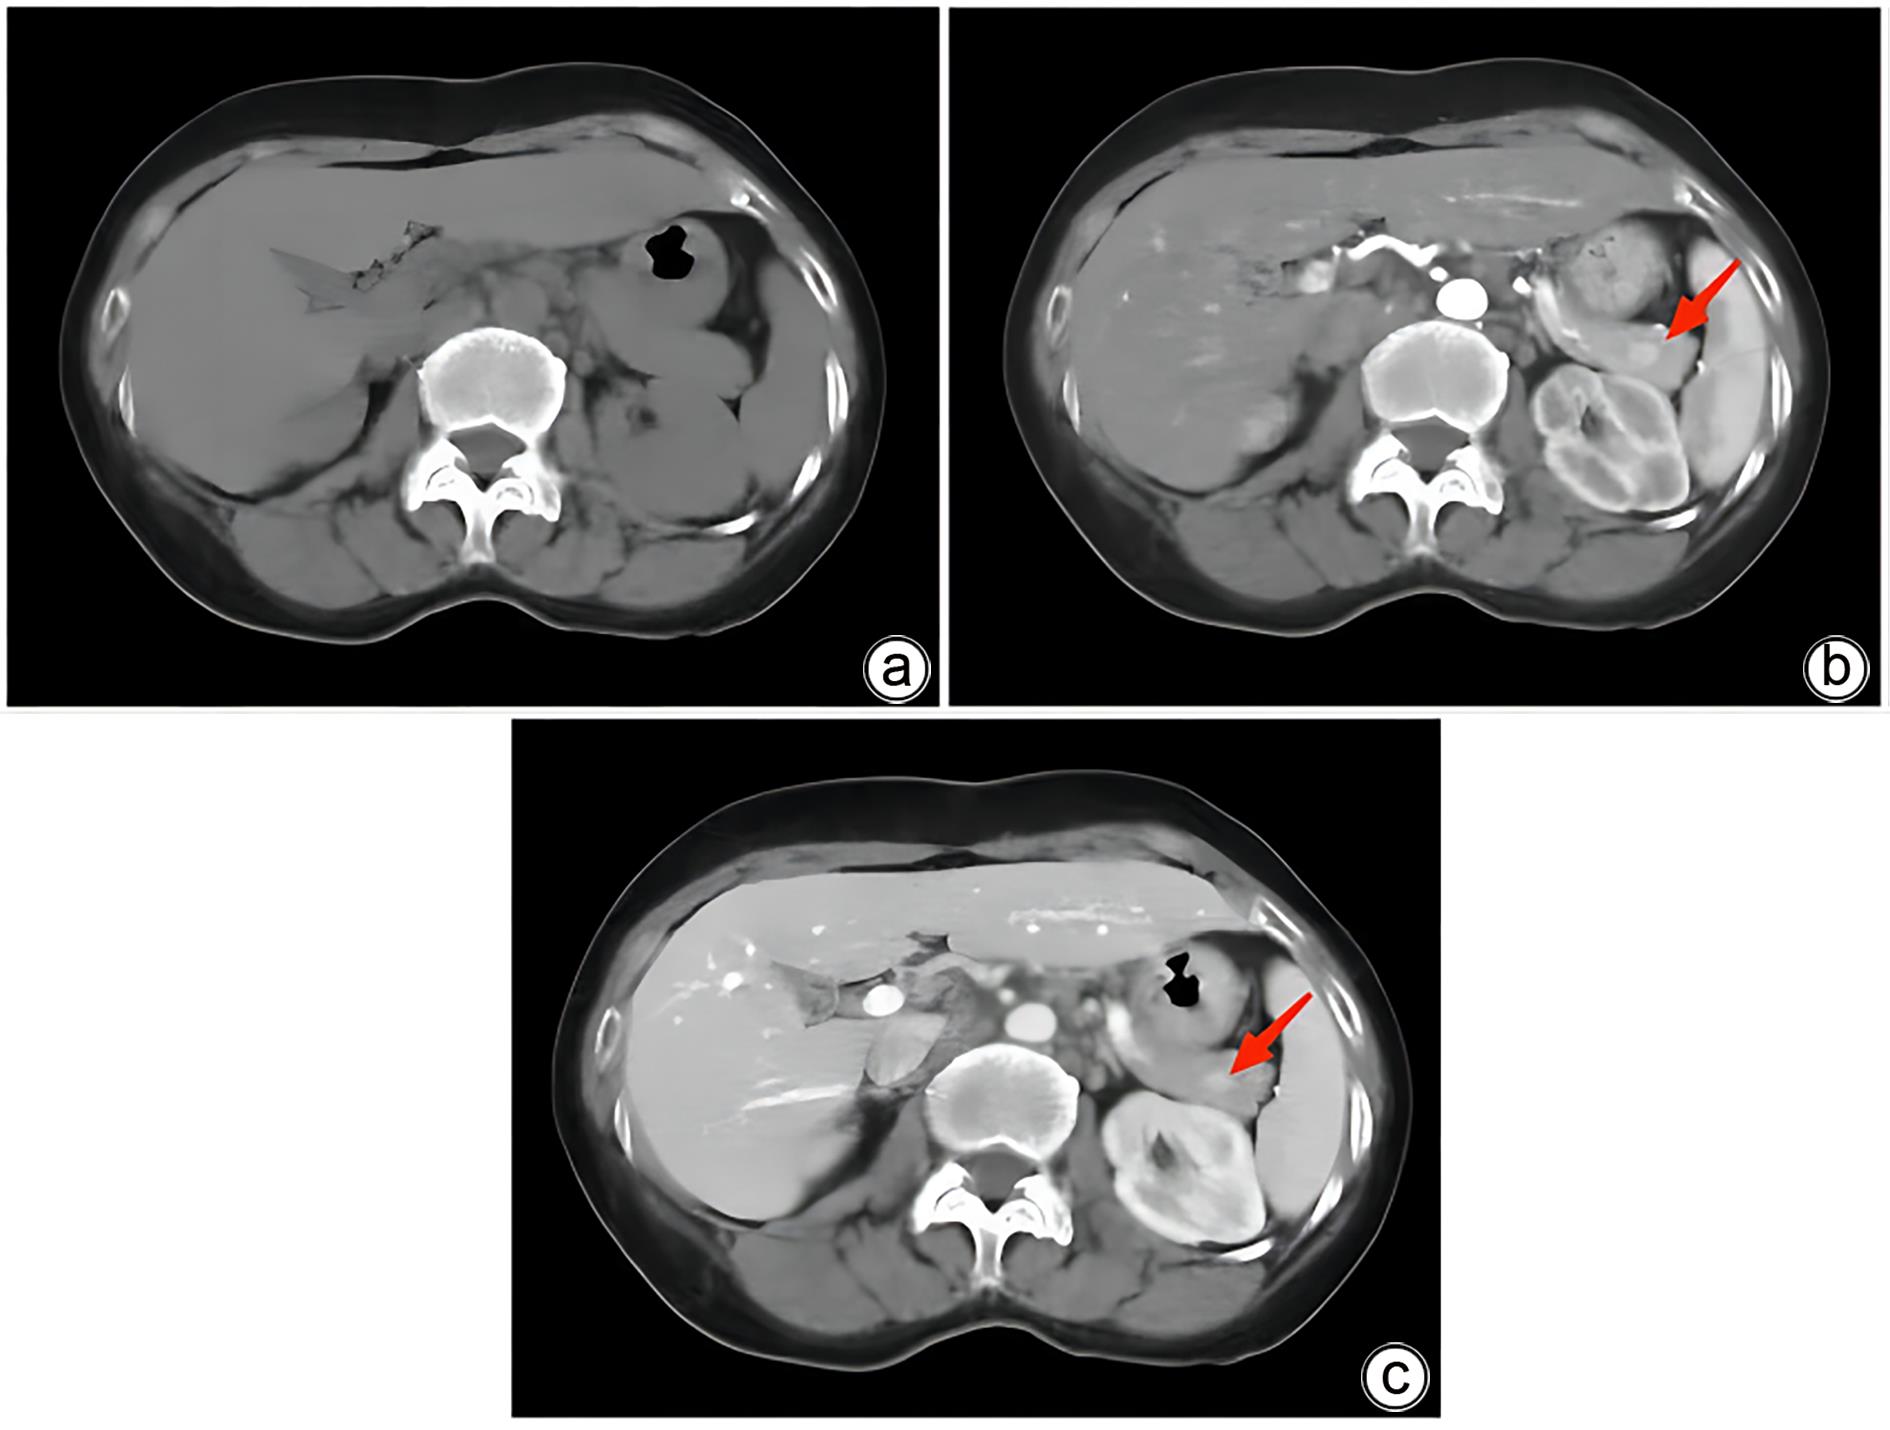

Misdiagnosis of intrapancreatic accessory spleen: A report of two cases

Mengzhe ZHANG, Jie RAO, Zhengle ZHANG

2024, 40(2): 365-368. DOI: 10.12449/JCH240223

Abstract(1384) HTML (333) PDF (1188KB)(176)

Abstract:

Accessory spleen refers to the spleen tissue that exists outside of the normal spleen, with a similar structure to the main spleen and certain functions. Intrapancreatic accessory spleen (IPAS) completely enveloped by the pancreas has an incidence rate of only 2%, and it is easily misdiagnosed in clinical practice due to its atypical clinical symptoms and similar radiological features to pancreatic neuroendocrine tumor, pancreatic solid pseudopapillary tumor, and other pancreatic space-occupying lesions. This article reports the clinical data of two patients with IPAS who were misdiagnosed as pancreatic neuroendocrine tumor and pancreatic solid pseudopapillary tumor, respectively, analyzes the reasons for misdiagnosis, and summarizes the experience in diagnosis and treatment, in order to improve the ability for the differential diagnosis of IPAS in clinical practice.